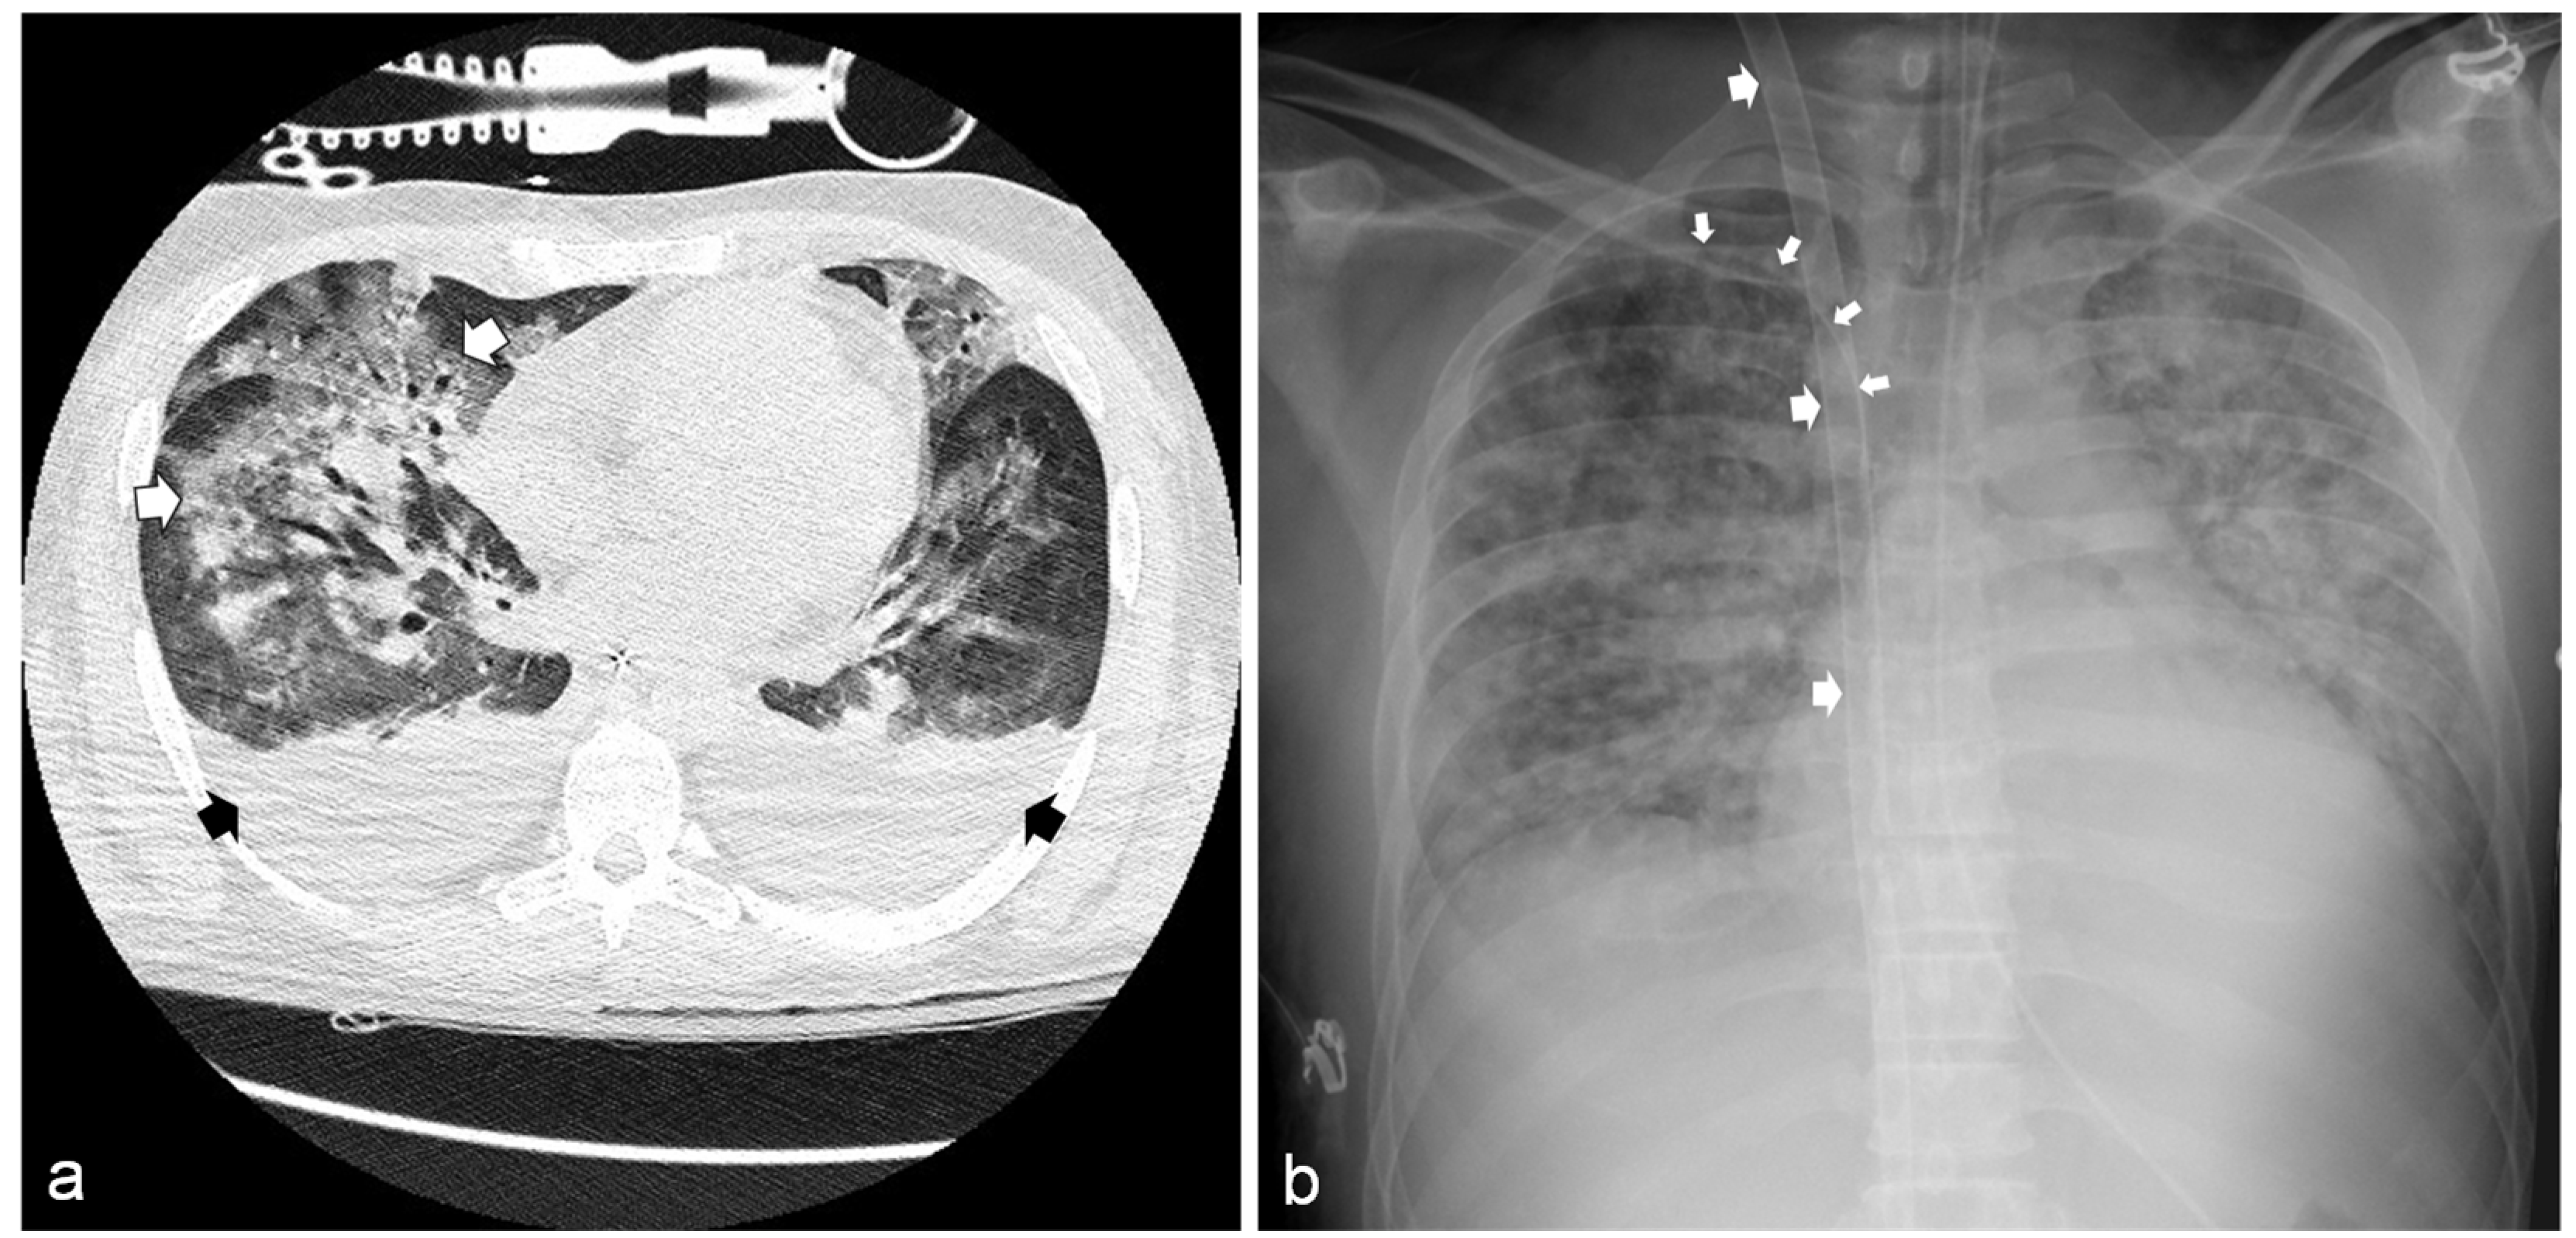

Chest X-ray and chest computed tomography (CT) scans showed bilateral pneumonia with ground-glass infiltrates (Figure 2a). Clinical and laboratory findings were consistent with the diagnosis of septic shock with multi-organ failure (MOF). Hemodynamic stability was restored through high-dose norepinephrine (up to 1.9 μg/kg/min). A broad-spectrum antibiotic therapy was also started (ceftazidime 4 g/day and meropenem 2 g/day). Nevertheless, a progressive, severe deterioration of respiratory functions was observed. Thirty-six hours after ED admission, the partial pressure of oxygen to fraction of inspired oxygen ratio (PaO2/FiO2) fell to 51.5, despite volume-controlled ventilation (FiO2 = 1; PEEP = 7 cm H2O; respiratory rate = 20 breaths/min; tidal volume = 500 mL); therefore, the ECMO team was immediately alerted, and the patient was admitted to the cardiac surgery ICU.

Figure 2.

(a) Chest computed tomography showing bilateral pleural effusion (black arrows) and diffuse ground-glass infiltrates (white arrows). (b) Chest radiography showing the bi-caval dual-lumen catheter placed in the right jugular vein (large arrows) and the central venous catheter in the right subclavian vein (small arrows).

After placing an Avalon Elite® Bi-Caval Dual-Lumen Catheter through the right internal jugular vein under trans-esophageal ultrasound guidance, a veno-venous ECMO (VV-ECMO) was started. A further triluminal central catheter was positioned through the right subclavian vein for hemodynamic and oxyphoretic monitoring and drug administration (Figure 2b).